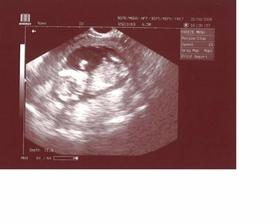

13.2. - Maminka mě vzala k panu doktorovi, abych mu ukázal srdíčko - byl moc spokojenej a říkal že jsem šikovnej mrňousek... musel teda mamince dvakrát ukázat, kde ten můj blikací puntík má hledat 😀 ale nedivte se jí - ona to ještě nikdy v životě neviděla 🙂 a pak ještě říkal, jak jsem veliký, ale mami si to nepamatuje ... jen pořád říkala, že jsem 7+3 ale deset mi prej neni ? a to jsem si myslel, že matematiku už umim ...